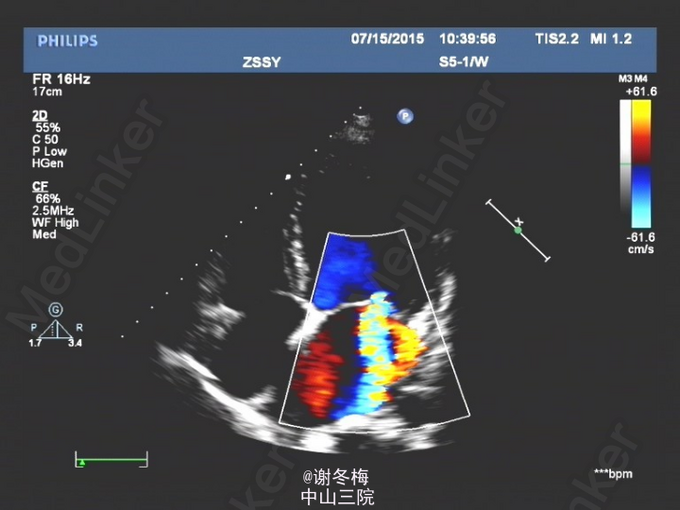

查体:BP108/69mmHg,神清,呼吸平顺,颜面、眼睑无浮肿,皮肤粘膜无苍白,甲状腺Ⅰ度肿大,质软,无触痛,未扪及结节,心率104次/分,律齐,各瓣膜听诊区未闻及明显杂音,双肺呼吸音粗,未闻及干湿性啰音,腹膨隆,腹软,无压痛、反跳痛,双足背动脉搏动可,双下肢无凹陷性浮肿。 辅查:2015-3-16我院行彩超心脏:左房、左室增大(左心房41mm,左室舒张末容积60mm),右房稍大,左室壁普遍性运动减弱,左心功能减低(EF 32%),二尖瓣反流(中重度)。三尖瓣反流(中重度)。主动脉瓣反流(轻度)。肺动脉高压(轻度)。心包积液(微量)。 Holter:1、窦性心律,2、偶发房性早搏,3、频发多源发室性早搏伴成对室性早搏(1836个),4、T波改变。 冠脉CT:1.LM近分叉处狭窄约20%(非钙化斑块);LAD近段钙化斑块,管腔未见狭窄;余冠状动脉CTA未见异常。2.左肺炎症。